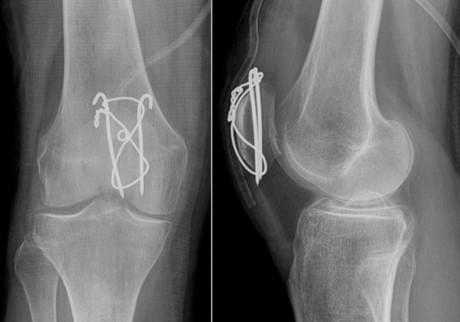

Спицами Киршнера в основном фиксируют мелкие кости и суставы (пальцы стопы и кисти, плюсневые и пястные кости). Иммобилизация проводится, как правило, в течение 4-6 недель после операции. Факсация может быть как наружной, т.е. конец спицы находится над поверхностью кожи, так и внутренней, т.е. спица полностью погружена под кожу для снижения риска инфицирования и неудобств пациента. Исполюзуется для временной фиксации. Так же существует погружной остеосинтез спицами и проволокой для остеосинтеза более крупных костей по Веберу, например, при:

Удаление спиц и проволоки после остеосинтеза надколенника по Веберу

При переломах надколенника (коленной чашечки) со смещением отломков выполняется операция остеосинтеза, т.е. скрепление костных фрагментов для восстановления целостности кости и соответственно функции коленного сустава. Так как при отказе от операции пациент рискует остаться инвалидом.

Для остеосинтеза надколенника в подавляющем большинстве случаев используется методика Вебера. Когда костные отломки скрепляются двумя титановыми спицами Киршнера и дополнительно стягиваются титановой проволокой 8 образно. Это позволяет быстро и очень эффективно восстановить поврежденную кость и что немаловажно металлоконструкция минимальна по стоимости. Но у нее есть один большой минус. Очень часто пациенты испытывают дискомфорт и боль в области мпиц и проволоки, так как она находится правктичекски сразу под кожей. Поэтому часто выполняется удаление металлоконструкции из надколенника.

После того как кость срослась и металлоконструкция выполнила свою функцию ее можно удалить. Полное сращение кости происходит за 6- 8 месяцев, в некоторых случая 1 год. Именно спустя этот срок можно удалять металл.

Перед данной операцией нужно выполнить стандартные анализы крови; список можно посмотреть здесь.

Операция зачастую выполняется в условиях дневного стационара, т.е. через несколько часов после операции пациент может уйти домой. Анестезия местная, проводниковая либо наркоз. Непосредственно сама операция по времени занимает 30 минут. Найти проволку и спицы, как правило, не представляет труда для хирурга. После того как металлоконструкция удалена проводится зашивание раны и наложение асептической повязки. Пациент приходит на перевязки в первые сутки, далее можно перевязываться самостоятельно либо в лечебном учреждении рядом с домом. Швы необходимо снять через 14 дней после операции. В раннем послеоперационном периоде назначаются обезболивающие и антибактериальные препараты.

Примерно через 1 месяц после операции по удалению металлоконструкции из надколенника можно постепенно увеличивать нагрузку и возвращаться в свой обычный ритм жизни.